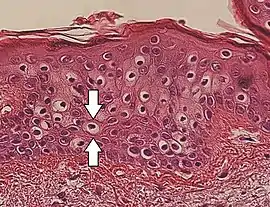

Perinuclear vacuolization of epidermal keratinocytes (one indicated by arrows), in this case an insignificant incidental finding.

Vacuolization is the formation of vacuoles or vacuole-like structures, within or adjacent to cells. Perinuclear vacuolization of epidermal keratinocytes is most likely inconsequential when not observed in combination with other pathologic findings. In dermatopathology "vacuolization" often refers specifically to vacuoles in the basal cell-basement membrane zone area, where it is an unspecific sign of disease.[1] It may be a sign of for example vacuolar interface dermatitis, which in turn has many causes.